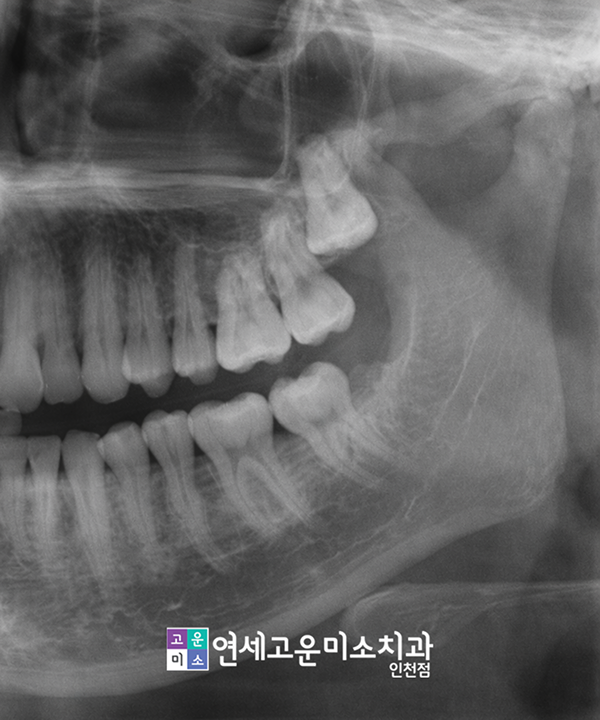

Q. 보통 어떻게 진단하나요?

치과에서는 보통 엑스레이로 치아가 신경과 얼마만큼 가까운 위치인지 파악합니다.

다만 경우에 따라 3차원적 진단지표가 필요하다면 구강 전용 3D-CT를 통해서 더 자세히 진찰합니다.